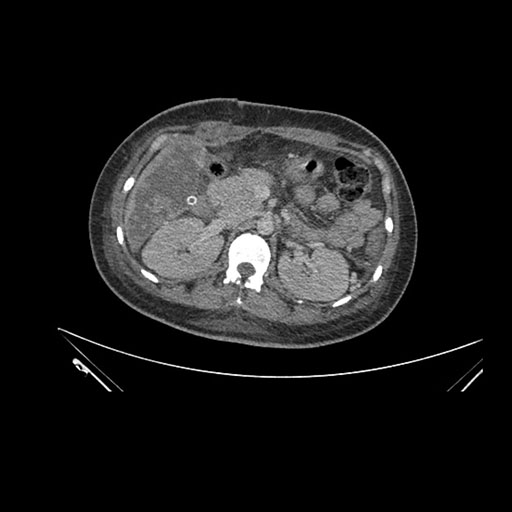

Axial Arterial

Imaging analysis

Based on initial findings, which issue(s) would you be most concerned about?